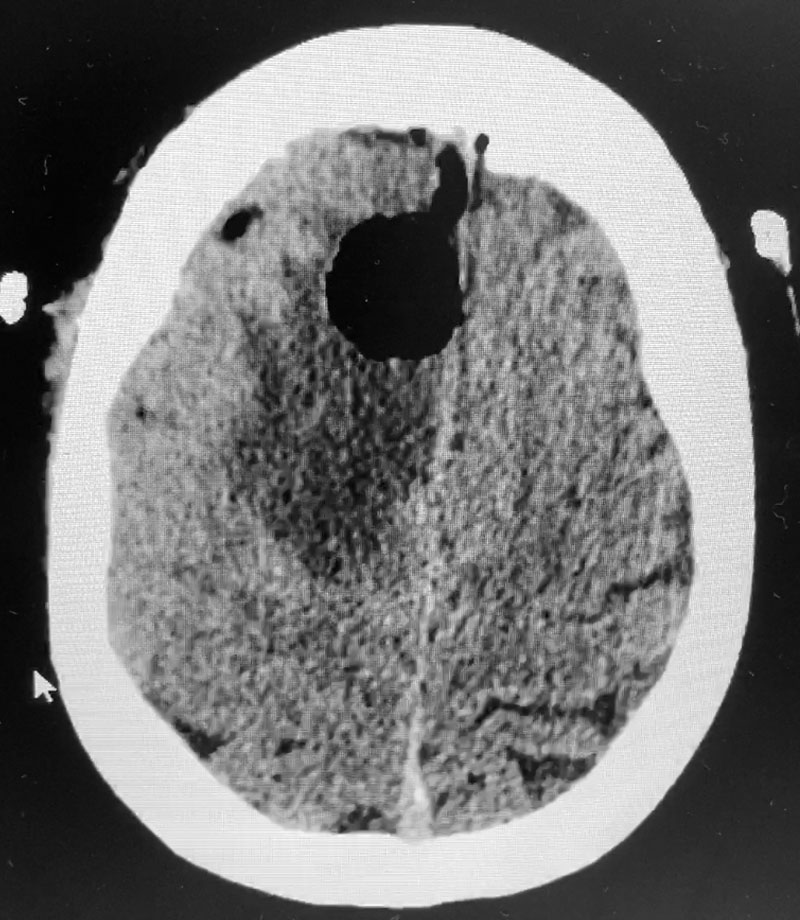

Postoperative images looked good (Figure 3). The patient felt better after surgery. His headaches were much better and he started to feel stronger. He was discharged after a brief hospital stay. He tapered his steroids to off. He will get follow up MRI images every few months. If tumor does recur, repeat radiosurgery would be performed.

Figure 3: Post operative CT scan.